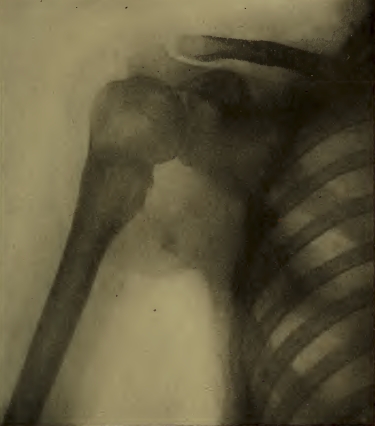

PLANCHE V. — Radiographie d'une épaule. Les parties des côtes qui sont les plus rapprochées de la plaque donnent des ombres nettes et étroites; les parties plus éloignées donnent des ombres moins nettes et élargies.

La planche V nous montre la radiographie d'un thorax, sur laquelle on reconnaît les déformations inévitables de la projection. Les côtes apparaissent très élargies dans leurs portions éloignées de la plaque, par rapport aux portions rapprochées de la plaque.

Pour réduire au minimum les déformations des images radioscopiques et radiographiques, il convient de les obtenir, autant que possible, en projection normale, c'est-à-dire en utilisant des rayons, dont la direction est, en moyenne, perpendiculaire à l'écran radioscopique ou à la plaque radiographique. Si, par exemple, la plaque est placée sur une table, au-dessus de laquelle se trouve l'ampoule, il est facile de s'assurer, à l'aide d'un fil à plomb, que la condition est approximativement réalisée. De plus, il y a avantage à appliquer sur la plaque la région à radiographier, de manière à ne point exagérer l'agrandissement; pour la même raison, on peut éloigner l'ampoule de la plaque autant que le permet la diminution d'intensité qui en résulte.